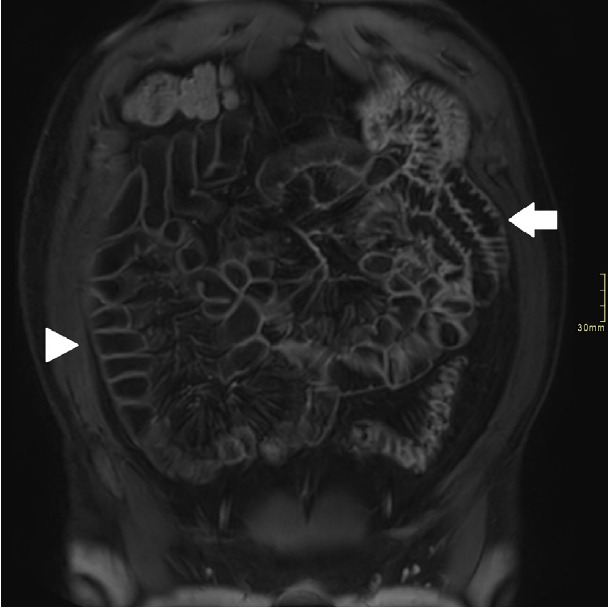

Background/aims: Assessment of quality of magnetic resonance enterography (MRE) in small bowel Crohn's disease (CD) activity evaluation has received little attention. We assessed the impact of bowel distention and motion artifact on MRE activity indices in ileal CD.

Methods: A cohort of patients who underwent contemporaneous MRE and colonoscopy for ileal CD assessment between 2014 and 2021 at 2 centers were audited. An abdominal radiologist blinded to clinical data reviewed each MRE, graded bowel distention and motion artifact upon a pre-specified 3-point scale and calculated the original magnetic resonance index of activity (MaRIA) and simplified MaRIA (sMaRIA), London index and CD MRE index (CDMI). Ileal endoscopic activity was graded via the Simplified Endoscopy Score for CD (SES-CD). The performance of MRE indices in discriminating active disease (SES-CD ≥3) stratified by MRE quality was measured by receiver operator characteristic analyses.

Results: One hundred and thirty-seven patients had MRE and colonoscopy within a median of 16 days (range, 0-30 days) with 63 (46%) exhibiting active disease (SES-CD ≥3). Forty-four MREs (32%) were deemed low quality due to motion artifact and/or moderate to poor distention. Low-quality MREs demonstrated reduced discriminative performance between ileal SES-CD ≥3 and MRE indices (MaRIA 0.838 vs. 0.634, sMaRIA 0.834 vs. 0.527, CDMI 0.850 vs. 0.595, London 0.748 vs. 0.511, P<0.05 for all). Individually the presence of any motion artifact markedly impacted the discriminative performance (e.g., sMaRIA area under the curve 0.544 vs. 0.814, P<0.05).

Conclusions: Image quality parameters can significantly impact MRE disease activity interpretation. Quality metrics should be reported, enabling cautious interpretation in lower-quality studies.